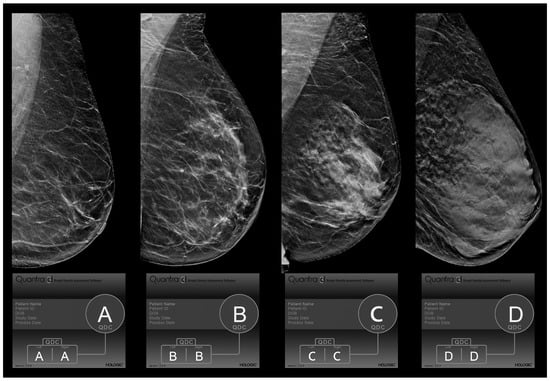

Breast Density Evaluation According to BI-RADS 5th Edition on Digital Breast Tomosynthesis: AI Automated Assessment Versus Human Visual Assessment

2.2. Visual Mammographic Density Assessment by Radiologists